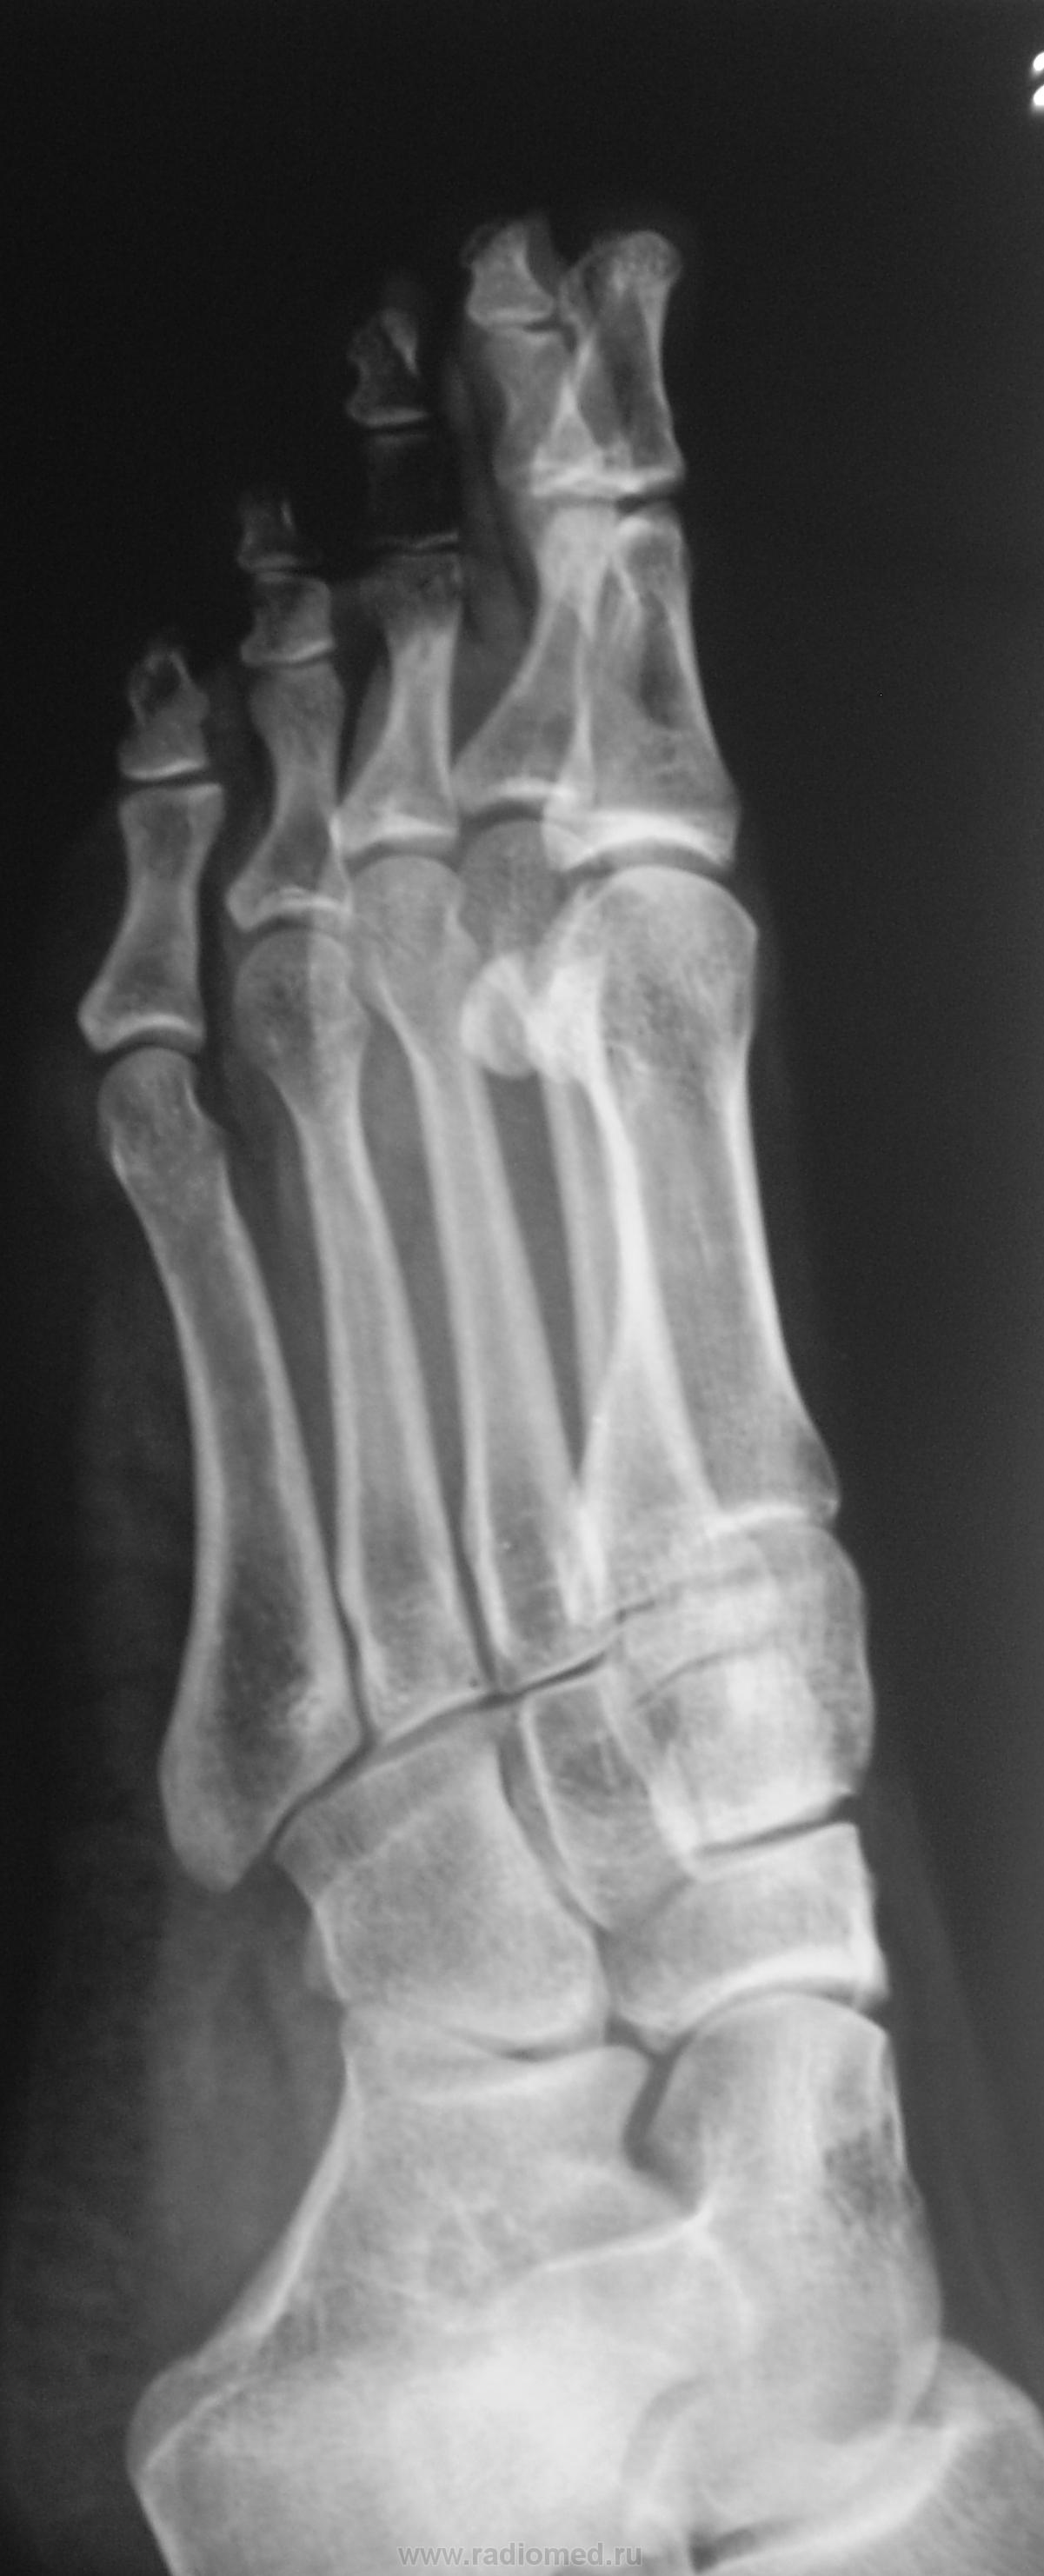

Фрагменты с увеличением.

Приложения:

Правую никак не смог разглядеть надо бы обработать получше. в левой старая связочная травма сустава Шопара, постттравматический небольшой подвывих пяточно-кубовидного сустава, следы почившего гемартроза там же. Травма эта не с лестницы вперед упала?

несросшийся перелом сесамовидной слева